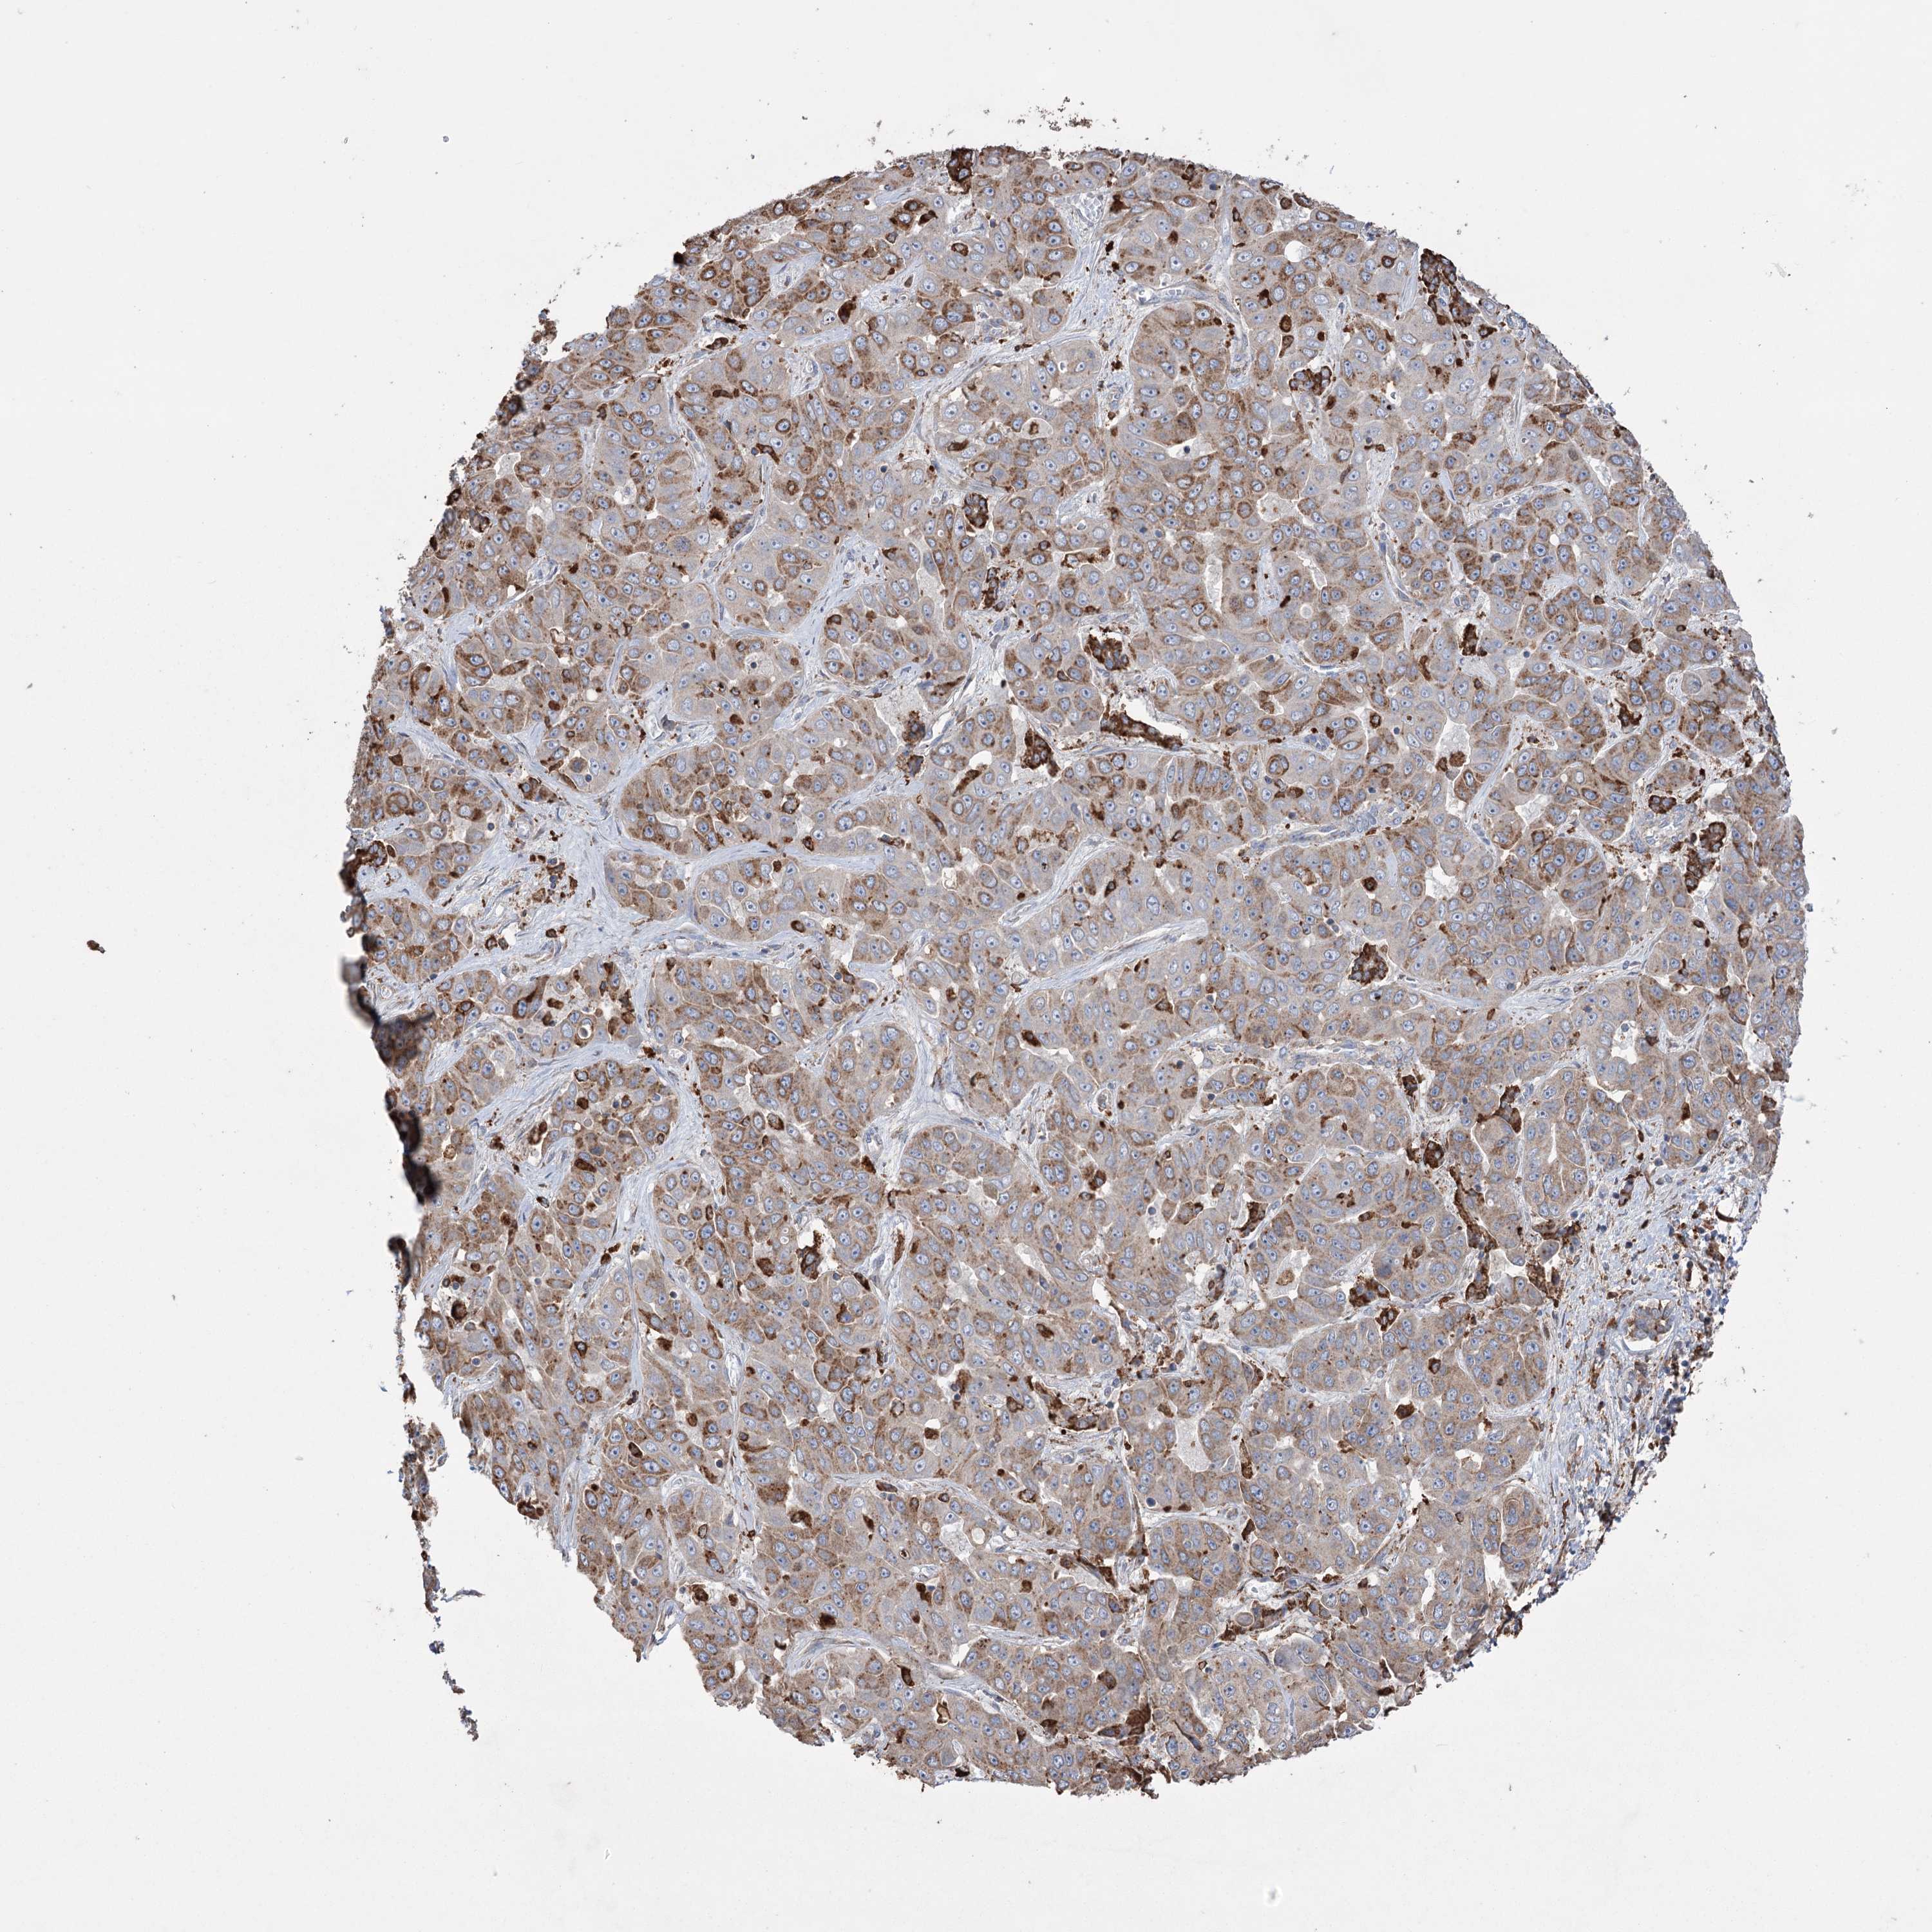

LIVER CANCER - Protein expressioni

A mouse-over function shows sample information and annotation data. Click on an image to view it in a full screen mode. Samples can be filtered based on level of antibody staining by selecting one or several of the following categories: high, medium, low and not detected. The assay and annotation is described here.

Note that samples used for immunohistochemistry by the Human Protein Atlas do not correspond to samples in the TCGA dataset.

Antibody stainingi

Antibody staining in the annotated cell types in the current human tissue is reported as not detected, low, medium, or high, based on conventional immunohistochemistry profiling in selected tissues. This score is based on the combination of the staining intensity and fraction of stained cells.

Each image is clickable and will lead to virtual microscopy that enables deeper exploration of all samples and also displays staining intensity scores, fraction scores and subcellular localization as well as patient and tissue information for each sample.

Antibody HPA038141

Antibody HPA038142

Staining

High

Medium

Low

Not detected

Intensity

Strong

Moderate

Weak

Negative

Quantity

>75%

75%-25%

<25%

None

Location

Nuclear

Cytoplasmic/membranous

Cytoplasmic/membranous,nuclear

Cholangiocarcinoma

Carcinoma, Hepatocellular, NOS